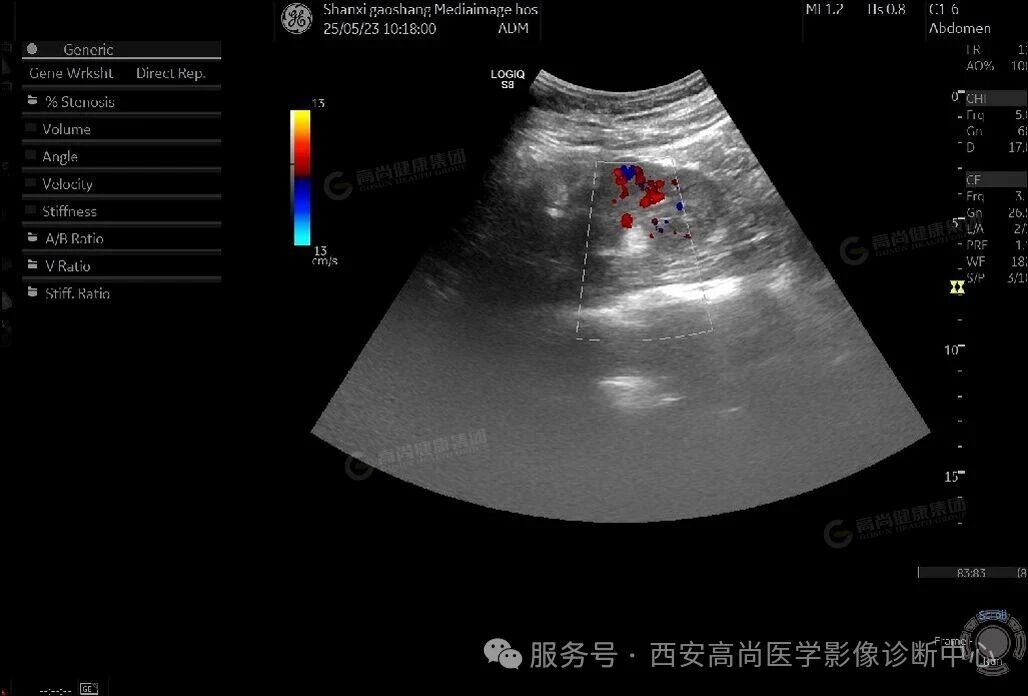

左肾高回声,考虑肾错构瘤(多发)

右肾高回声,考虑肾错构瘤(单发)